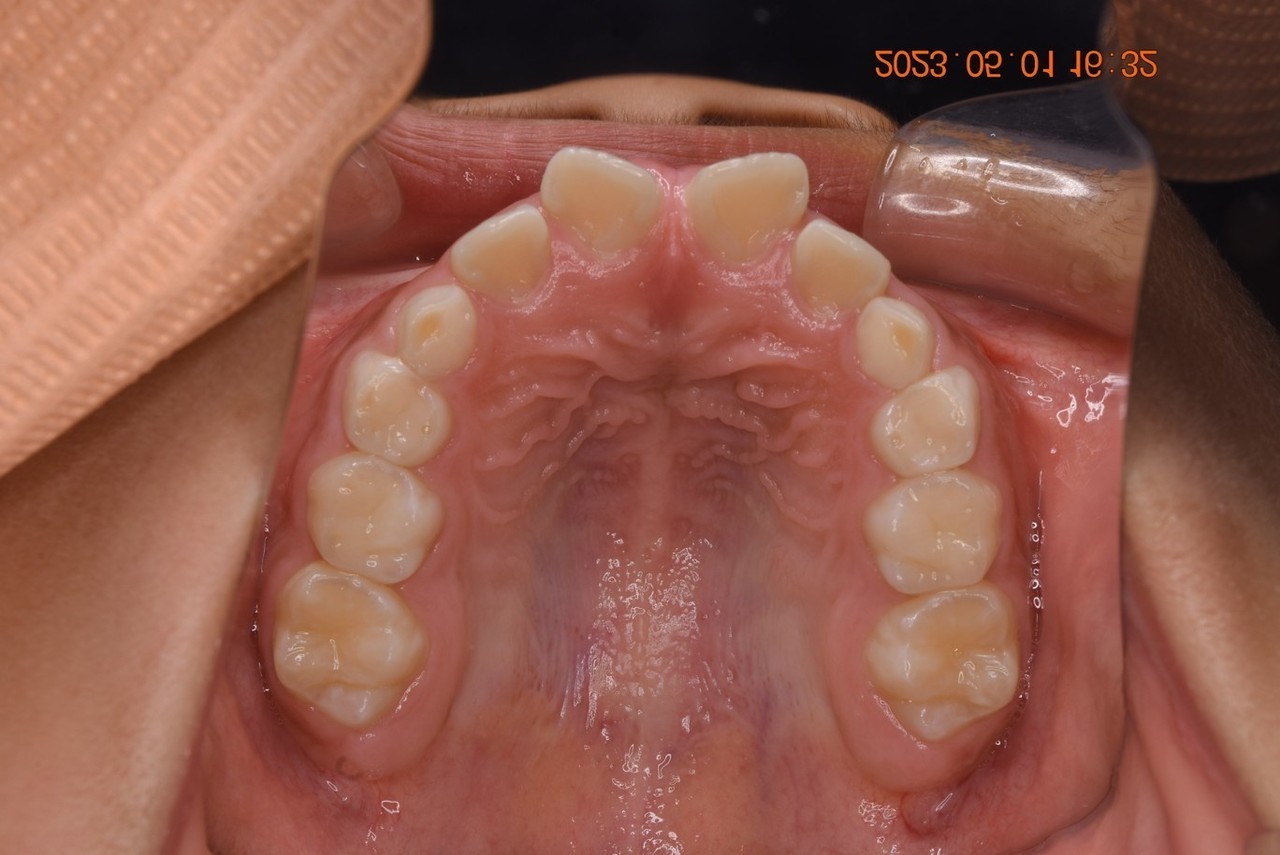

08:出っ歯と奥歯の傾き(シザースバイト)があった方

矯正治療の症例写真

矯正治療終了後の症例写真

保定期間の写真

症例・治療内容について

• 主訴:出っ歯と奥歯が傾いている、歯が交叉して噛み合うところがある

• 診断あるいは主な症状:上顎前突、交叉咬合

• 年齢:25歳(治療開始年齢)

• 治療に用いた主な装置:マルチブラケットによる歯列矯正

• 抜歯部位:上下の4番目の歯

• 治療期間:3年2ヶ月

• 通院回数:41回(矯正治療を目的とした来院)

• 治療費概算:950,000円(税込)